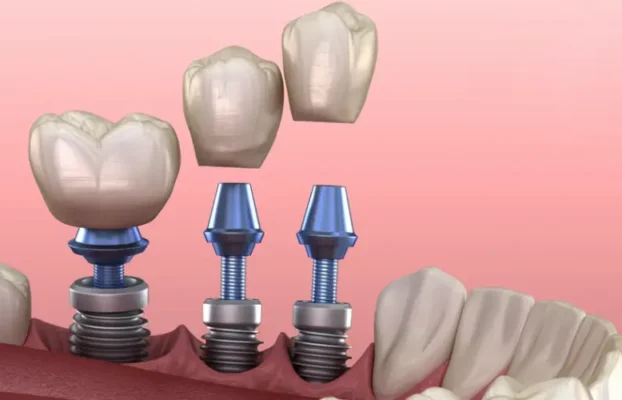

قرار دادن ایمپلنت دندان شامل جراحی برای قرار دادن یک پایه فلزی در استخوان فک شما است. با گذشت زمان (معمولاً 6 ماه) پست با استخوان اطراف خود پیوند می یابد. این به عنوان یک لنگر برای نگه داشتن یک یا چند دندان از دست رفته در جای خود عمل می کند.

ایمپلنت های دندانی گزینه های درمانی عالی برای افرادی هستند که دندان های خود را از دست داده اند. آنها می توانند یک دندان یا بسیاری از دندان ها را جایگزین کنند (ایمپلنت های بیشتری برای مناطقی که چندین دندان از دست داده اند مورد نیاز است). مطالعات طولانی مدت در مورد طول عمر ایمپلنت های دندانی انجام شده است و در بیماران سالم غیر سیگاری و دیابتی، موفقیت 10 ساله در محدوده 95 درصد و بالاتر در برخی مطالعات گزارش شده است.

انواع ایمپلنت دندان بر مبنای روش کاشت دندان به 4 گروه تقسیم می شوند:- ایمپلنت های اندواستیل

- ایمپلنت های ساب پریواستیل

- ایمپلنت های یک مرحله ای

- ایمپلنت های دو مرحله ای